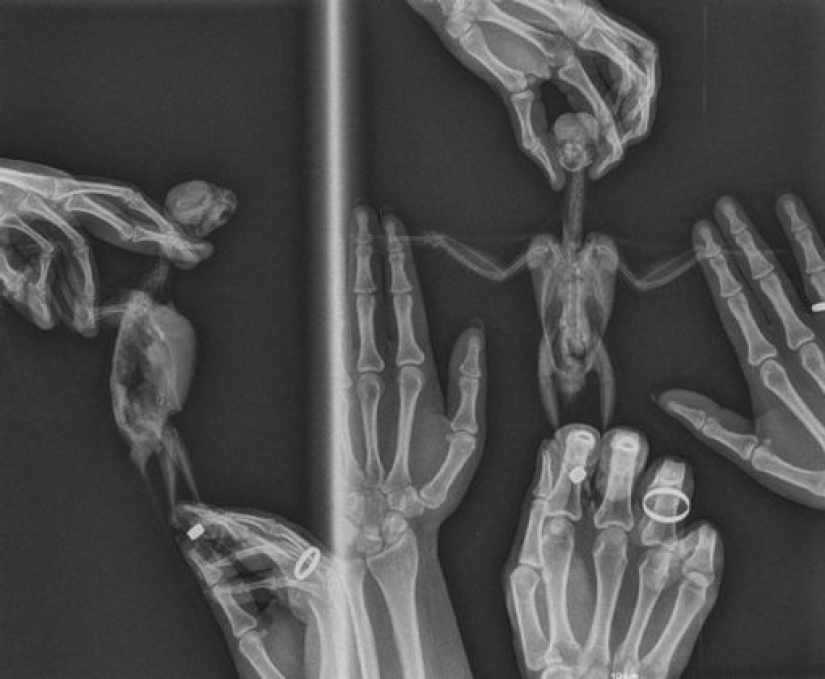

1. “This is how a parrot is x-rayed. The bird is alive and well. The procedure was done by a veterinarian and we were there to help keep our pet.”

8. "We made a beautiful Halloween card."